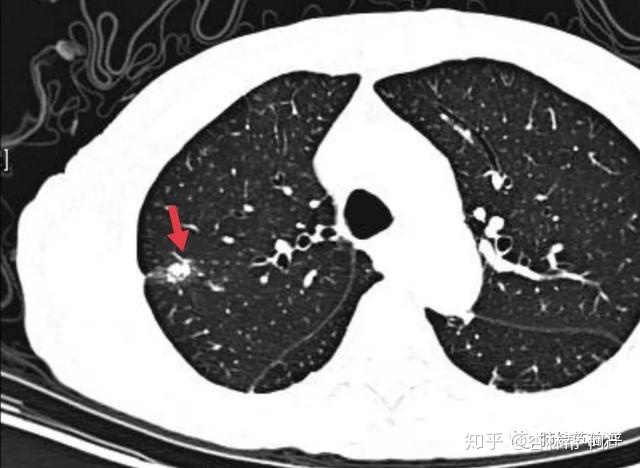

结节3:8mm实性结节,长毛刺,三角形,为良性表现。但是有血管进入,能排除肺癌么?不敢。

结节3:CT值为185,诊断为良性纤维灶结节。

这个右上肺结节CT值也很高>200,但是其周边出现了磨玻璃影,为贴壁样生长的肺癌。术后病理为:微浸润腺癌。因此,纤维灶附近出现边界清楚的磨玻璃影,也是需要警惕的。